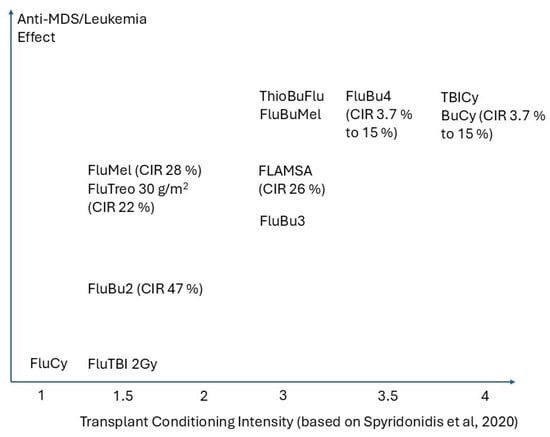

Allogeneic Stem Cell Transplantation: The Relevance of Conditioning Regime Intensity for Myelodysplastic Syndromes (MDS)

Curr. Oncol. 2025, 32(6), 319; https://doi.org/10.3390/curroncol32060319 - 30 May 2025

Allogeneic hematopoietic cell transplantation (alloHCT) is the sole curative therapy for myelodysplastic syndrome (MDS). While alloHCT clearly confers a significant survival advantage in high-risk MDS, it is less clear how the disease burden and impact of conditioning intensity impact survival. This review addresses

Allogeneic hematopoietic cell transplantation (alloHCT) is the sole curative therapy for myelodysplastic syndrome (MDS). While alloHCT clearly confers a significant survival advantage in high-risk MDS, it is less clear how the disease burden and impact of conditioning intensity impact survival. This review addresses critical issues surrounding this topic, emphasizing the unique cell biology of MDS and the evolving concepts of conditioning intensity compared to other diseases, including acute myeloid leukemia (AML). The review is structured around three interconnected themes. First, it clarifies the varying interpretations of conditioning intensity. Second, it examines the interplay between disease burden at transplant and conditioning intensity in determining outcomes, including a comparative analysis with acute myeloid leukemia (AML) to highlight similarities and differences. Third, it explores the relationship between conditioning regimen intensity and immune reconstitution, particularly focusing on the graft-versus-tumor (GvT) effect and its potential modulation by conditioning intensity. Understanding the stem cell target of conditioning regimens is emphasized, as the persistence of the underlying MDS stem cell necessitates a thorough understanding of this concept for improved therapeutic strategies.